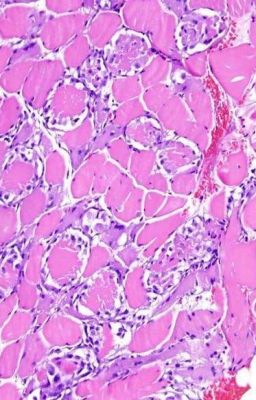

Арсений- доктор на подстанции скорой помощи/ Дима его друг и коллега...